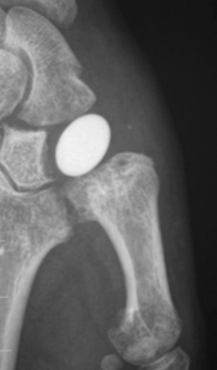

Implant d'interposition

Ablation du trapèze et mise en place d'un implant en pyrocarbone